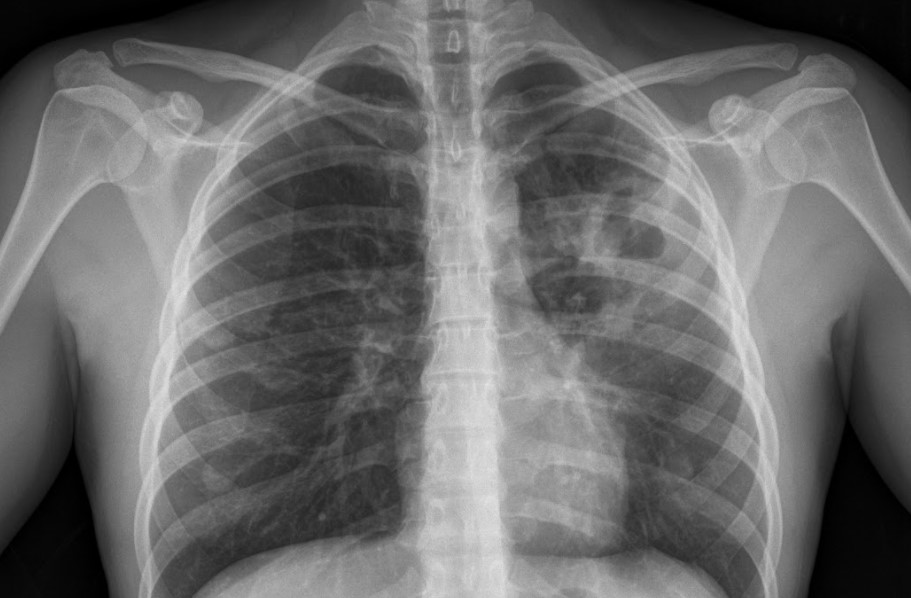

La neumonía es una infección del pulmón que puede ser causada por diferentes gérmenes como bacterias, virus y hongos. Es la infección que con mayor frecuencia justifica el ingreso de un paciente en el hospital y la causa mas frecuente de muerte de origen infeccioso. Se clasifican según se adquieren en el ámbito extrahospitalario (neumonía […]